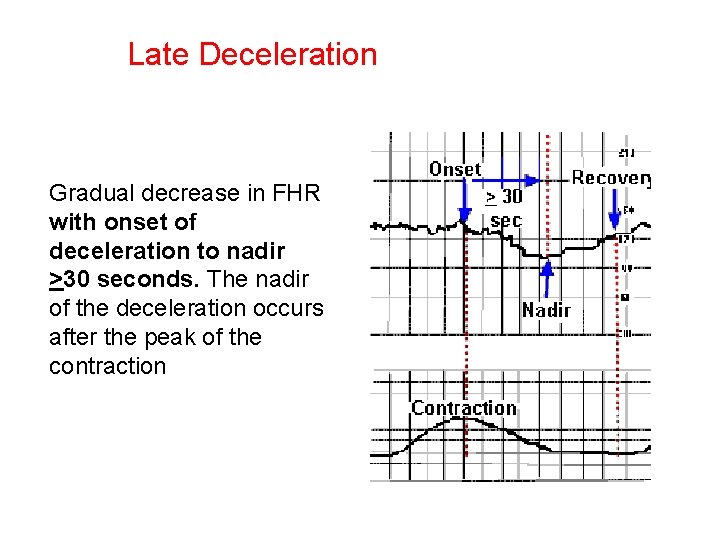

Late Deceleration Gradual decrease in FHR with onset of deceleration to nadir >30 seconds. The nadir of the deceleration occurs after the peak of the contraction